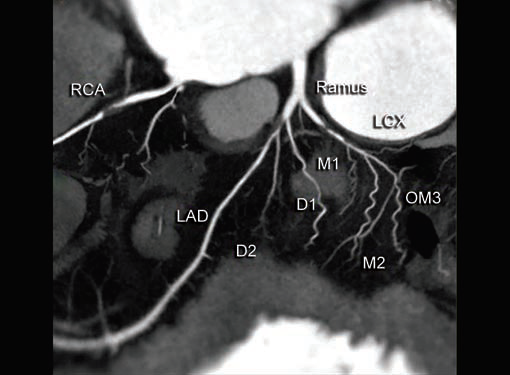

Coronary stenosis (Fig. 4) can be detected efectively.

Degree of stenosis is categorized as minimal, mild, moderate

and marked. Diagnostic accuracy falls as one goes down

to distal part of vessel as caliber decreases. Ostial stenosis

LM and right coronary artery (RCA) can be picked. Rarely

detection of ostial lesion may be the sole purpose of CT, after

an inadequate evaluation of ostia on catheter angiogram.

Even in CT, evaluation of ostial lesion is hard as compared

to diagnosis of segmental stenosis.

CT is the preferred tool of investigation of coronary bypass grafts (Fig. 9). Reversed saphenous vein grafts (SVGs) are optimally studied consistently. Anastomotic sites are studied effectively. However, distal anastomosis of venous graft to obtuse marginal branch (OM) is relatively difficult to evaluate because of diminishing caliber of native vessel. Arterial grafts pose a small challenge due to artifacts of associated surgical clips (Figs 10A and B). Ostium and proximal part of graft are assessed well. However, distal anastomotic site may be difficult to assess on occasions. RIMA graft, posterior descending artery (PDA) graft, gastroepiploic artery graft can also be studied. Stenosed venous grafts

can be stented and the same can be evaluated by CT (Fig. 11). Like native RCA, RCA grafts (Figs 12A and B) are more susceptible to motion artifacts when compared to LAD and OM grafts. Catheter angiogram can be used to answer specific queries after CT angiogram.

Most commonly involved vessel is LAD. Proximal and mid segment are affected. Classified into superficial and deep types. OM is the second most commonly involved vessel. Bridging is a small piece of information surgeon would be happy to know about, before CABG.